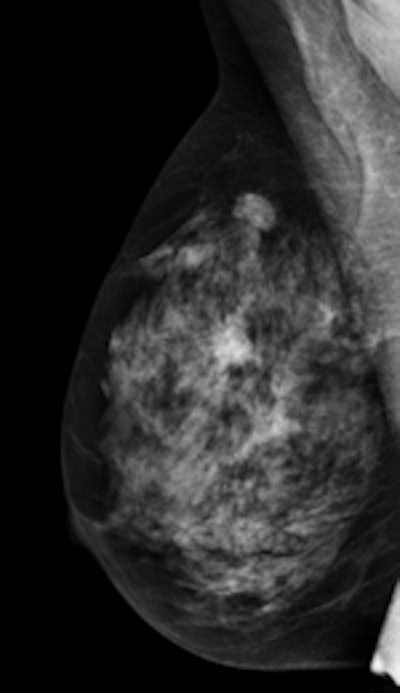

Routine tests are recommended to ensure the image quality assessed at the mammography system's installation remains unchanged. Current guidelines suggest a simple phantom -- plastic material of appropriate thickness equal to absorption of a typical breast -- and a single detail to produce a large-area-signal against the surrounding background on the resulting image is enough to test reproducibility performance.

However, the use of a single parameter extracted from a single phantom image is statistically limited and accounts weakly for the normal fluctuations in the image formation process, they wrote. Commercial phantoms are an alternative; they contain several details, a series of low- and high-contrast details, differences in size and shape, spatial resolution patterns, and step wedges for contrast resolution evaluation. Also, appropriate algorithms capable of analyzing phantom images and measuring one or more objective image quality indexes from each detail available in the phantom are appropriate.

Layout of the Leeds TOR MAS test object. The test plate includes 12 circular details 5.6 mm in diameter, with nominal contrast diminishing from 8.3% to 0.15%, for low-contrast sensitivity measurements; 11 circular details 0.5 mm in diameter and 11 0.25 mm; a step wedge with 8-mm square strips producing a 10-point scale for contrast and dynamic range evaluations; three five-point step wedges incorporating small irregular-shaped particles for noise measurements at different contrasts; a high-contrast resolution grating, with 26 groups of bar patterns in a range of spatial frequencies from 1.0 lp/mm to 20.0 lp/mm.Software tools to measure image quality from phantom images improve sensitivity and precision of measurements, compared with human-based measurements, and variations of the image quality indexes over time can be used to monitor long-term reproducibility of a mammography unit and detect possible meaningful variations.

Gennaro and colleagues used the commercial phantom TOR MAS (Leeds Test Objects) to test the reproducibility of 25 digital mammography systems in their regional screening program. They used the web version of automatic software tool AutoPIA (automatic phantom image analysis; CyberQual) to analyze phantom images and produce 60 quantitative image quality indexes. They selected 15 for comparison with image quality index reference values and for assessment of image quality reproducibility over time.